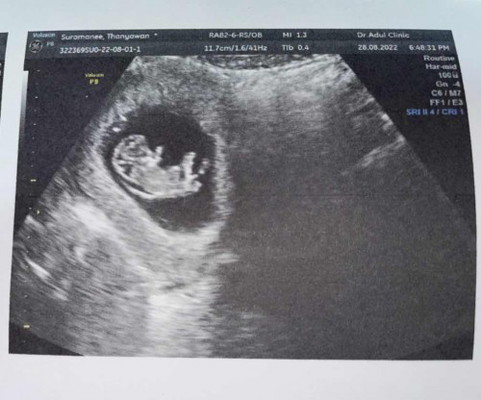

มีใครอัลตราซาวด์แล้วคอหนาแบบนี้บ้างคะ

วันนี้ไปอัลตราซาวด์มา 10วีค แล้วหมอแจ้งว่าดูจากอัลตราซาวด์แล้วมีความเสี่ยงเป็นดาวซินโดม เพราะคอน้องหนา เรากลัวมากเลยค่ะกลัวเขาเป็นสงสารเขา มีแม่ๆคนไหนอัลตราซาวด์แล้วคอหนาบ้างคะ แล้วตรวจเป็นรึป่าว